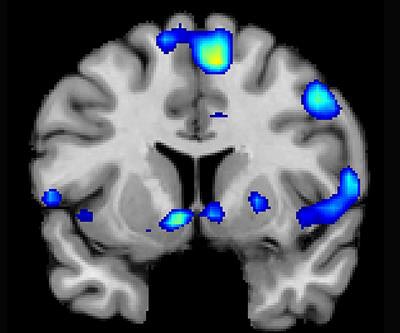

When people have a religious and spiritual experience, reward-related regions of the brain become illuminated on functional MRI (fMRI) scans, much the same way these areas react to love, sex, gambling, drugs, and music, according to a study published November 29 in Social Neuroscience.

The spiritual feelings were associated with activation in the nucleus accumbens, which is associated with processing reward, as well as in brain regions associated with focused attention. Such feelings were also linked with activity in the medial prefrontal cortex, which is activated by tasks involving valuation, judgment, and moral reasoning.